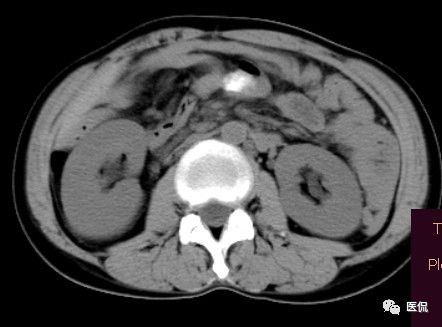

女 40岁 ,10年前做个剖腹产术。之后到现在一直感觉肚子疼,去很多医院做检查 诊断肠结核,经过反复抗结核治疗。病人10年瘦了几十斤。

腹腔内残留的纱布在人体内引起渗出或液化坏死并纤维包裹形成异物性脓肿(纱布瘤)。纱布瘤的影像特点:圆形或卵圆形肿块,较大,有完整包膜,薄壁,较少的情况下为厚壁,边界较完整,增强后薄膜可以持续强化。不同时期的纱布瘤可以有不同表现:早期(10个月或半年内)多表现为蜂窝状;2~5年内一般表现为囊性飘带状;10~20年之后则为实性软组织密度,包膜钙化呈钙化网状结构。手术过程中残留在人体内的医用纱布所形成的肿瘤样病变。